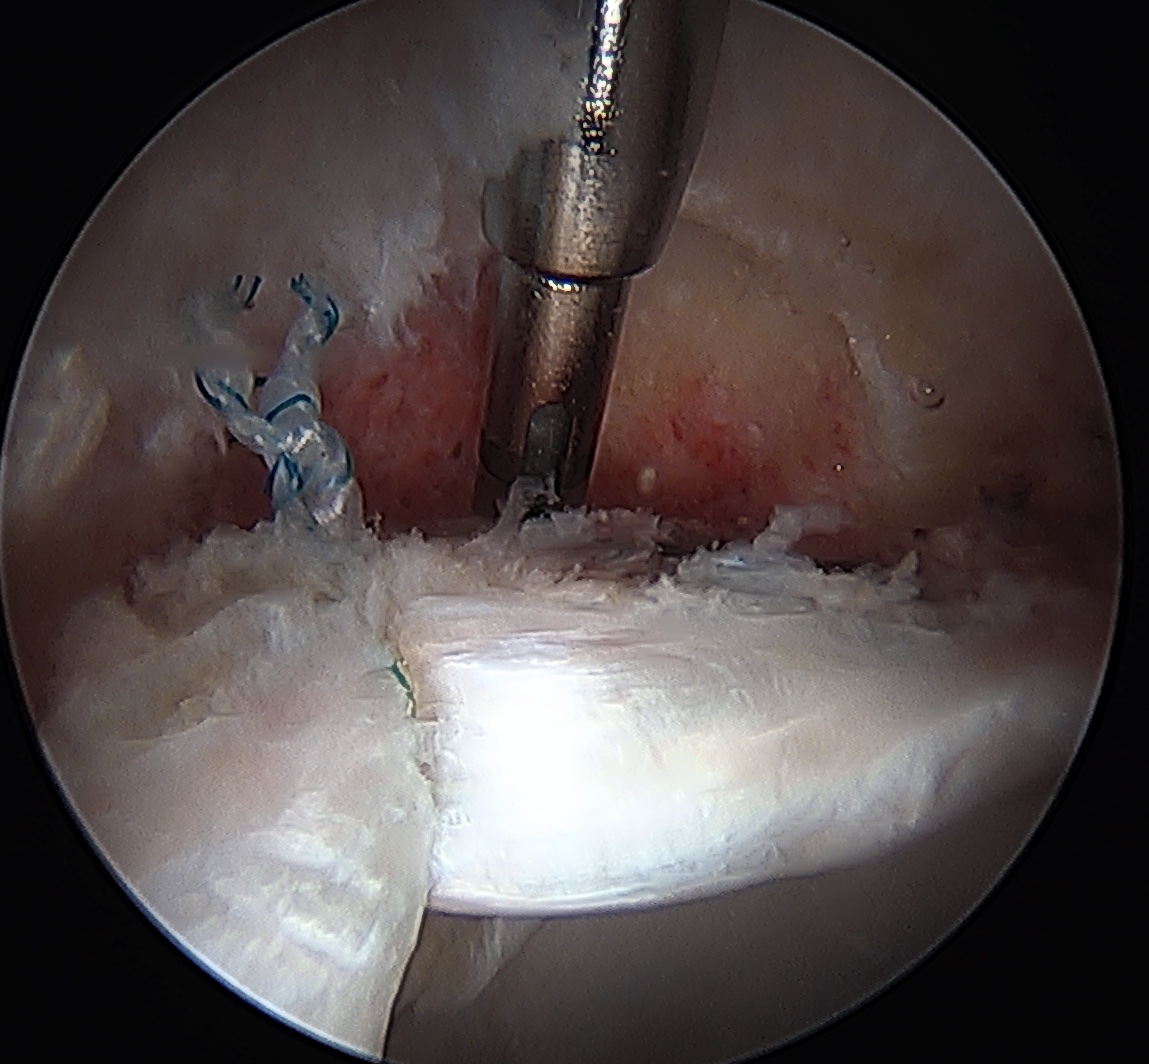

CAM resection

Capsule

- distal capsule suspension sutures / parachute technique

- T capsulotomy - better for large Cam lesions, needs repair

Placing distal capsule sutures to allow parachute technique / distal capsule suspension to expose Cam

T capsulotomy to expose large Cam at head neck junction

Anterior Cam

- hip flexed to 45 degrees

- image intensifer rotated 20 degrees posterior and 20 degrees distal to allow Dunn view

Anterior cam resection with hip flexed

Intra-operative Cam resection using Dunn view

Lateral Cam

- hip in extension / internal rotation

Lateral cam resection with hip in extension